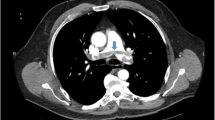

He visited our hospital’s out-patient department with a fever (> 38 °C) that started 2 days ago. He had no concomitant symptoms including respiratory distress symptoms. He had a blood pressure of 108/62 mm Hg, a heart rate of 77 bpm, a respiratory rate of 20 bpm, and an oxygen saturation at room air of 95%. The laboratory data were as follows: white blood cells (WBC), 8100/μL (neutrophils, 7023/μL; lymphocytes 535/μL); C-reactive protein (CRP), 5.6 mg/dL; procalcitonin, 0.05 ng/mL; and IL-6, 6.4 pg/mL. His kidney allograft function was stable (serum urea nitrogen of 17 mg/dL and serum creatinine of 1.52 mg/dL). A computed tomography (CT) scan revealed multiple regions of focal ground-glass opacity (GGO) in both lung fields (Fig. 1 A-C). The possibility of pneumocystis pneumonia was ruled out by the normal range of serum β-D glucan levels, while the possibility of cytomegalovirus was ruled out by a negative finding in the cytomegalovirus antigenemia assay. The patient was diagnosed with COVID-19 by the positive finding in the antigen testing for severe acute respiratory syndrome coronavirus 2 (SARS-CoV-2) (1930 pg/mL).

On day 7, his temperature increased to over 38.0ºC; however, the laboratory findings deteriorated as follows: WBC, 10,000/μL (neutrophils, 8000/μL; lymphocytes, 1050/μL); CRP, 6.9 mg/dL. A CT scan performed on day 10 revealed that the GGO regions were enlarged in both lung fields (Fig. 1 D-F). We also checked the D-dimer level, which had increased to 6.2 µg/dL from 1.0 µg/mL at the time of the diagnosis. We evaluated the myocardial enzyme levels and electrocardiogram, but both examinations yielded normal findings. Although the patient was not on bed rest, an ultrasonography of the leg blood vessels revealed DVT in both the right soleal and peroneal veins. (Fig. 2 A, C). The patient was therefore started on intravenous heparin (10,000 units daily), according to the guidelines from the National Center for Global Health and Medicine in Japan [18]. However, we gradually increased the dose of heparin up to 15,000 units daily to extend the activated partial thromboplastin time into the target range (50–70 s), according to our protocol (Fig. 3). Although he did not undergo any specific therapy for COVID-19 (e.g., remdesivir, tocilizumab, and antibody administration), successful clearance of SARS-CoV-2 was confirmed on day 16 (Fig. 3). We resumed MMF (1000 mg daily) on day 16. D-dimer levels improved to baseline levels after introducing anticoagulant therapy (Fig. 3). The patient was discharged on day18, and his anticoagulant therapy was switched to rivaroxaban (10 mg daily), which was continued for 2 months. Ultrasonography performed 2 months after the discharge revealed that the thrombus had disappeared from both vessels.